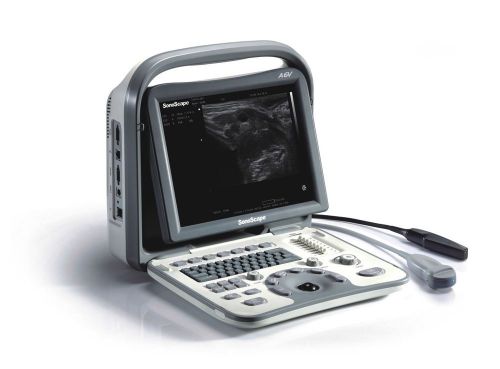

SonoScape A6V best Portable Veterinary Ultrasound with micro convex probe C612

SonoScape A6 Portable Ultrasound&linear array probe L745 deal